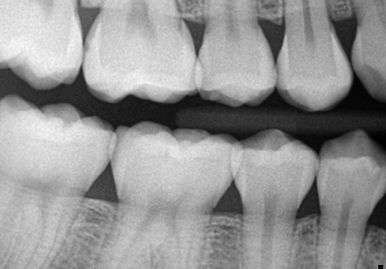

These are the most common type of dental X-rays for children. They show the upper and lower back teeth and are used to detect cavities between teeth. Bitewing X-rays are quick and comfortable, even for young children.